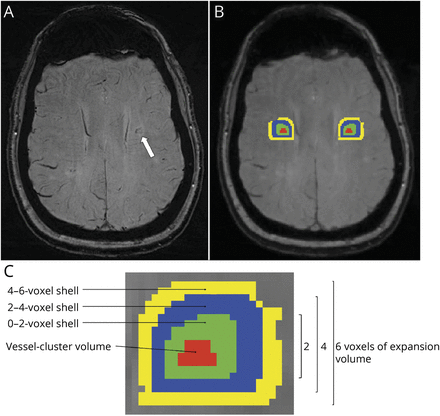

最后,评估表格大小和延迟vessel-clusters和周围的组织,从原始vessel-cluster分割,生成3额外同心环形vessel-clusters 3 d扩张(壳),每个2压厚T2-w空间(接近1体素在表格数据)局限于白质,提出图2。然后,我们自动生成contralateral-mirrored段在白质内,检查这些准确的镜像位置,如果需要手动编辑(提到过和狭义相对论)。FLS的软件16用于屏蔽处理。

(一)vessel-cluster用一个白色箭头指示susceptibility-weighted成像(瑞士)在左侧椎体semiovale CADASIL患者。(B)体积由vessel-cluster红色所示图片处理查看器(目前)。额外的同心壳卷(在0 - 2、2 - 4和4 - 6压vessel-cluster分割)使用不同的颜色来表示(分别为绿色、蓝色和黄色),生成三维内白质(C代表面积包括vessel-cluster体积的增大分割)。Contralateral-mirrored卷(用相同的颜色表示)生成侧半球的分析。注意,该决议在瑞士(A)高于nifti-file-converted图片处理观众(目前)。前者用于定性分析,而后者只获得量化措施。